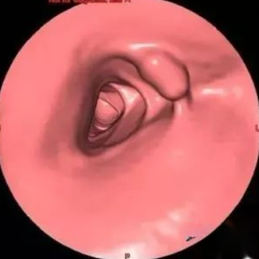

CT仿真肠镜

传统肠镜

CTC观察到中央上方隆起性病变

传统肠镜可见中央上方肠癌